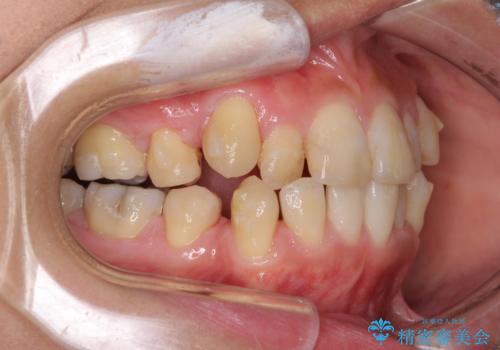

- 上下の八重歯を気にして来院された患者様です。

八重歯の後ろの歯を1歯抜歯し、補助装置(リンガルアーチ)を用いて八重歯の位置を改善し、その後インビザラインにより矯正治療を行うこととしました。

右側のみ上下小臼歯を抜歯したため、上下の正中が右にずれてしまう可能性があります。

また、元々右側は上下が咬み合っていないため、矯正をしても咬み合わないことも考えられました。